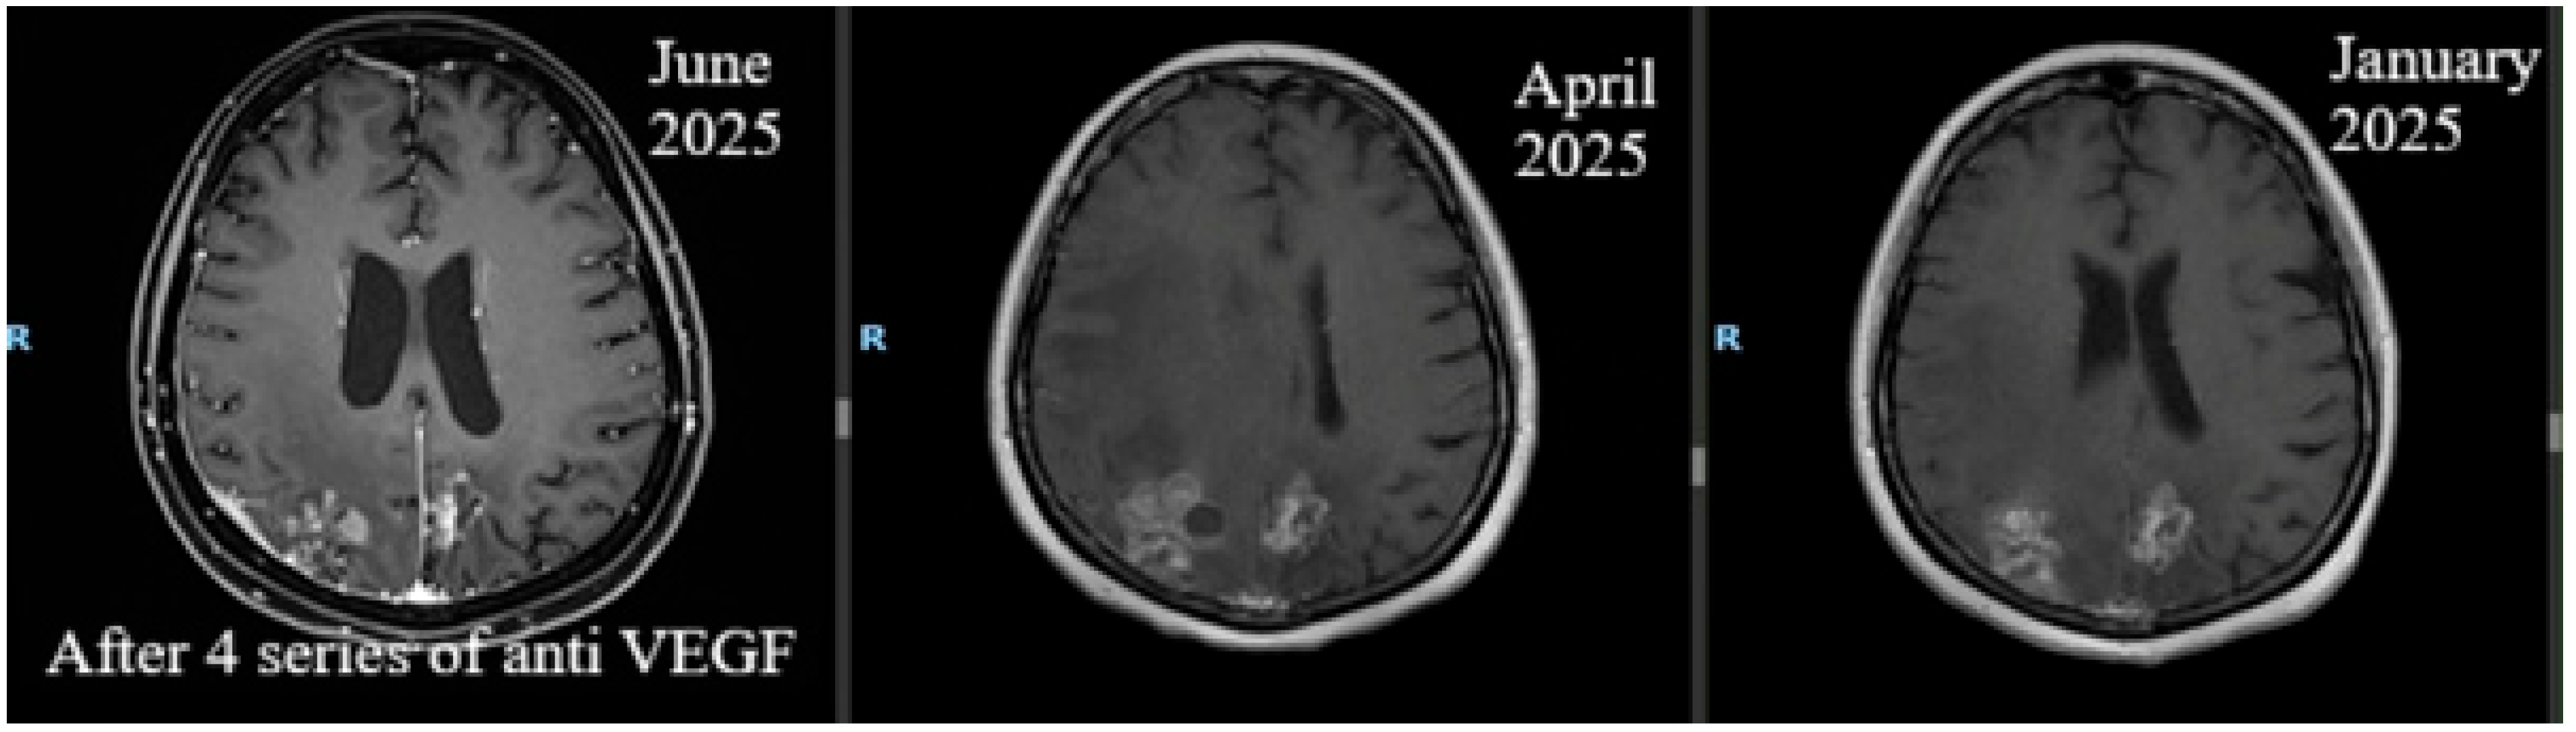

| 6. | 2025 | May: neurologic hemiparesis clinical status of 4/5 brachial and 3/5 crural; possible walking with unilateral support; Karnofsky Performance Status (KPS) = 60–70%. May–July: 4 cycles of bevacizumab 400 mg/cycle, KPS = 80–90%. July: brain perfusion MRI showed improved intra-axial post-therapeutic changes, but pachymeningeal thickening persisted. October: PET-CT showed no metabolic activity. The patient refused injectable systemic oncological treatment and continued and continued with Fulvestrant and ovarian suppression therapy. |